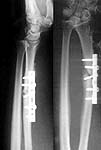

A male 42 years old, an anesthesiologist, was operated in a city hospital 11 month ago - ORIF of the radial shaft. All seemed to be OK, but last three months he marked pain and mobility at the fracture site. I viewed him and found apparent clicking when pressed over the plate as well as while rotation. He has flex/ext deficiency about 10-15 degrees in both directions, and almost full range of rotation. Recent x-rays (attached) also shows slight radial shortening which wasn't present at previous films. He still can work but strongly inclined to solve the non-union. I plan to remove the plate and insert a titanium nail, maybe with grafting. What is your opinion about the case?

Tissues under the plate were gray and black due to metallosis, so i just debrided the area, left interfragmentary tissue intact and applied circular ex-fix (x-rays attached) without grafting. This must be enough for the pattern of hypertrohic nonunion. After slight tension the distal RU joint looks OK. See attachment for the result of the surgery.